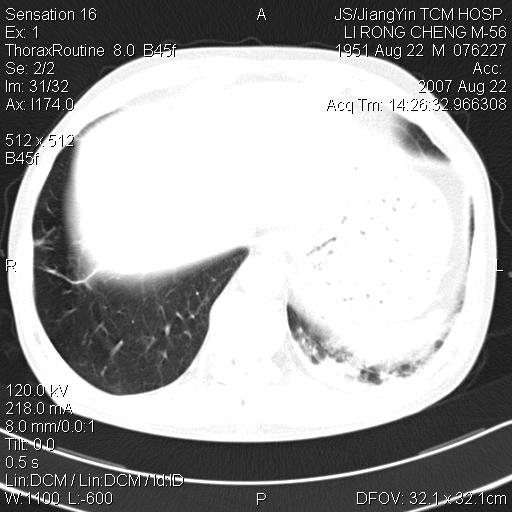

标题: CT9479:M,56Y,DM病史,咳嗽发热5天.肺脓疡.肺癌? [打印本页]

边灶边缘较光整,冠状位病灶呈大片状,,内有空洞,有胸膜反应,但无明显胸膜外侵犯征像,结合病史支持考虑肺肿脓,不排除结核,治疗后复查

好多钙化灶哦,病灶位于下叶背段,或许考虑结核更合适,做下相应检查先

左肺下叶见类软组织密度影,其内密度不均,有小空洞,广基与胸膜相连,其周见斑片状致密影.

考虑肺肿脓,不排除结核.

左肺下叶支气管呈小囊状扩张。下叶背段有类圆形高密度影,边缘模糊,外与胸膜相连。左侧胸膜增厚粘连。心包膜增厚。结合病史考虑1支扩并感染2胸膜及心包炎。

左下肺团片状类软组织密度影,形态不规则,边缘欠规整,其内可见液化区及气体影,病灶内侧见引流支气管影,相邻胸膜反应性增厚。病灶周围肺野内见增粗支气管,壁厚,边缘模糊。考虑:支气管扩张并感染;肺脓肿。